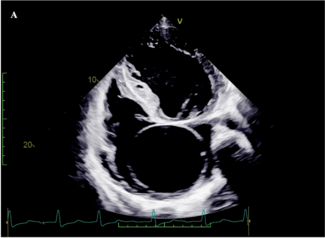

A 25-year-old man came to our clinic with complaints of exertional palpitations and dyspnea. He had skeletal features suggestive of Marfan’s syndrome.